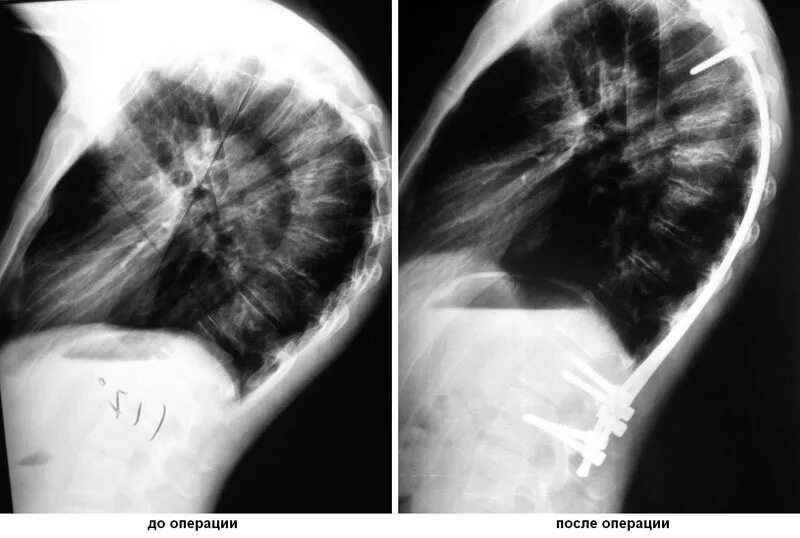

Болезнь шейермана мау что